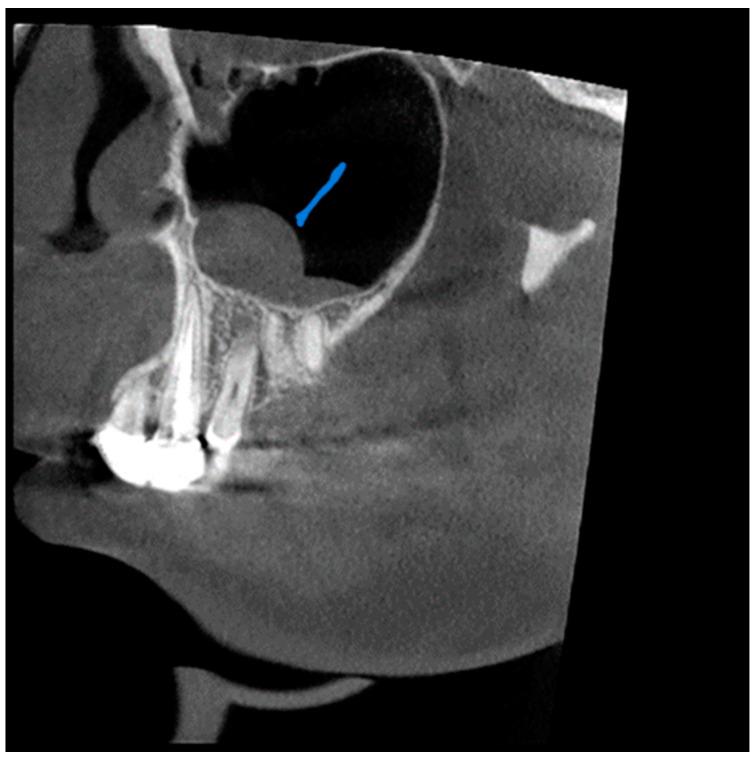

尽管锥形束计算机断层扫描(CBCT)在区分软组织方面存在局限性,但它对牙科手术产生了重大影响,并给我们的诊断和治疗计划方法带来了重大变革。它是一种出色的成像方式,能快速识别鼻窦混浊,并为鼻旁窦病变提供有价值的见解,且辐射暴露量低得多。本研究旨在调查CBCT扫描中上颌窦异常的发生率,确定这些发现的频率、类型和位置,并找出根尖周病变距离与上颌窦影像学变化之间的相关性。两名检查人员独立评估了117例患者,以诊断并将病例分类为不同的异常亚型。记录与鼻窦关系最密切的根尖周病变。记录左右上颌窦口的直径以及窦口下缘至鼻窦骨底的距离。将这些发现与这些患者的年龄和性别相关联。本研究表明,61例患者被诊断为黏膜增厚(52.1%)。受黏膜增厚影响最大的鼻窦壁是上颌窦底,其次是内侧壁和外侧壁。在19例有根尖周病变的患者中,15例有上颌窦黏膜增厚,这具有统计学意义(P = 0.004)。上颌窦异常的高发生率强调了放射科医生全面解读CBCT图像中获取的整个容积(包括整个鼻窦)的重要性。偶然发现可在个体的症状和体征临床背景中予以考虑,以降低高估影像学发现实际影响的风险。

https://cdn.ncbi.nlm.nih.gov/pmc/blobs/9100/10528184/18e7111ca61a/diagnostics-13-02918-g005.jpg